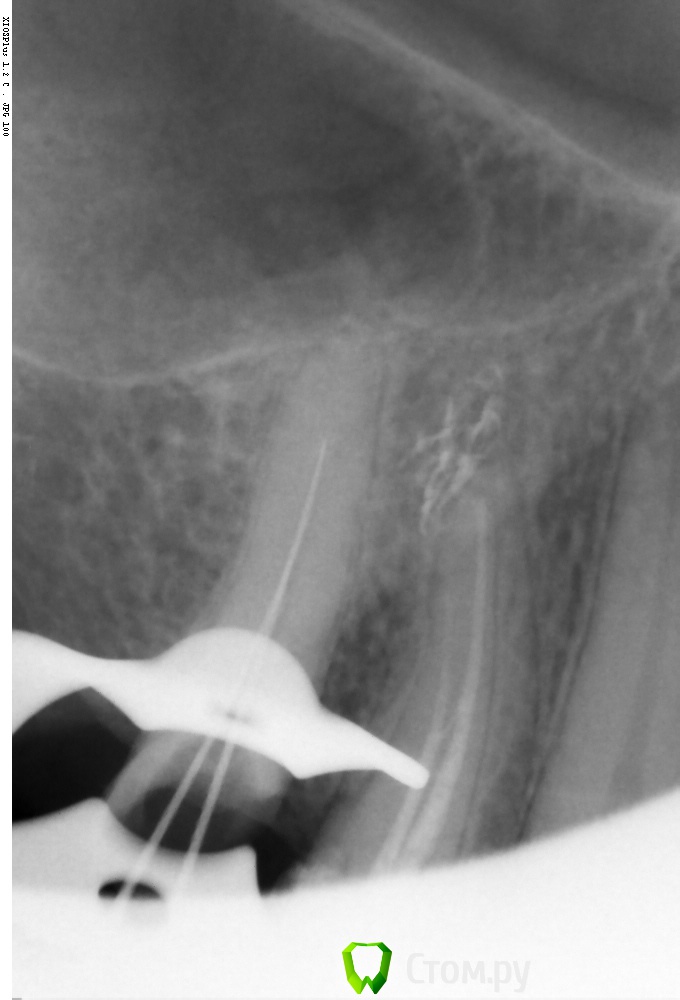

Shaid Опубликовано 18 мая, 2014 Поделиться Опубликовано 18 мая, 2014 (изменено) Вот какой тут будет прогноз?Долбил канал в два посещения. Петенси нет Изменено 18 мая, 2014 пользователем Shaid Ссылка на комментарий

Rash163 Опубликовано 18 мая, 2014 Поделиться Опубликовано 18 мая, 2014 Вот какой тут будет прогноз?Долбил канал в два посещения. Петенси нет Бессимтомник?Если да, то все будет хорошо) Ссылка на комментарий

Shaid Опубликовано 20 мая, 2014 Поделиться Опубликовано 20 мая, 2014 (изменено) Да. Ортопед направил перелечить. Пац ходит с кальцием сейчас, перкуссия слабоболезненна(до лечения безболезненно) Изменено 20 мая, 2014 пользователем Shaid Ссылка на комментарий